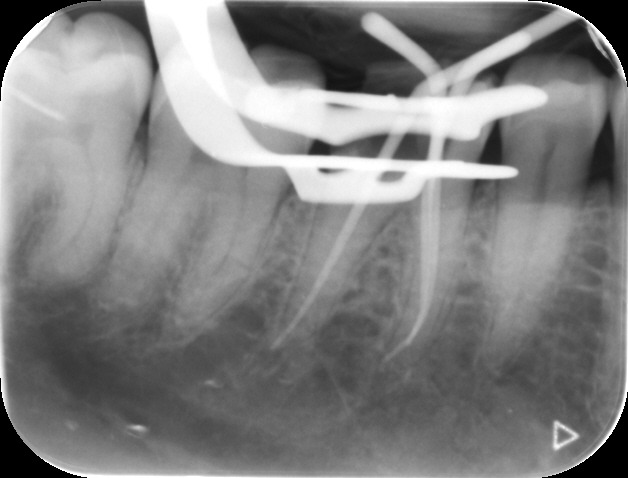

Files of different sizes are used to eliminate bacteria and infection and to shape the canals. The canals are disinfected thoroughly with irrigants and later the canals will be sealed in 3 dimensions with a special medicament called gutta-percha to prevent reinfection of the tooth and the access cavity will be sealed with a temporary filling.